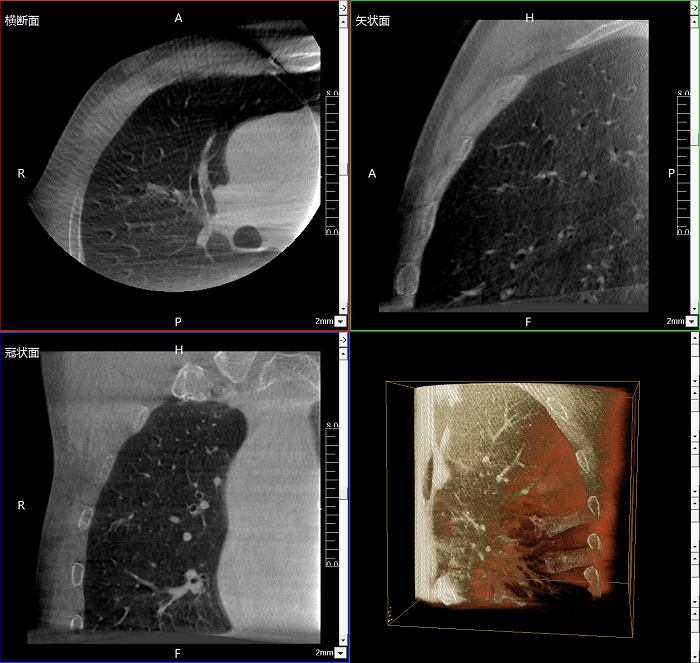

400萬像素成像

易于觀察細(xì)微病灶,利于胸部、腹部、脊柱關(guān)節(jié)等復(fù)雜骨骼和軟組織的成像。

Clinical picture

臨床圖片